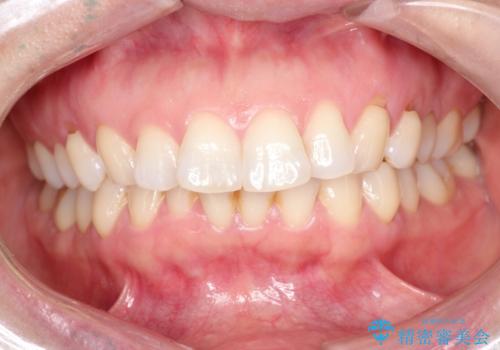

審美装置を用いたワイヤー矯正|非抜歯で歯の凸凹を改善

- 患者様は**歯の凸凹(叢生)**を気にされて来院されました。診査の結果、歯列のスペースが不足しているものの、抜歯をせずに改善できる状態でした。そこで、目立ちにくい審美装置(白いブラケットとホワイトワイヤー)を使用したワイヤー矯正を提案しました。歯列のアーチを広げながら、適宜IPR(歯の幅をわずかに調整する処置)を行い、非抜歯で自然な歯並びへと導く計画を立てました。

治療では、白いブラケットとホワイトワイヤーを使用し、矯正装置が目立ちにくいよう配慮しました。歯列を拡大しながら適切に歯を移動させ、IPRを併用することで、無理なくスペースを確保しました。見た目に配慮しながら、歯の凸凹をスムーズに整え、噛み合わせも改善。患者様からは「装置が思ったより目立たず、歯並びがきれいになって嬉しい」との声をいただきました。